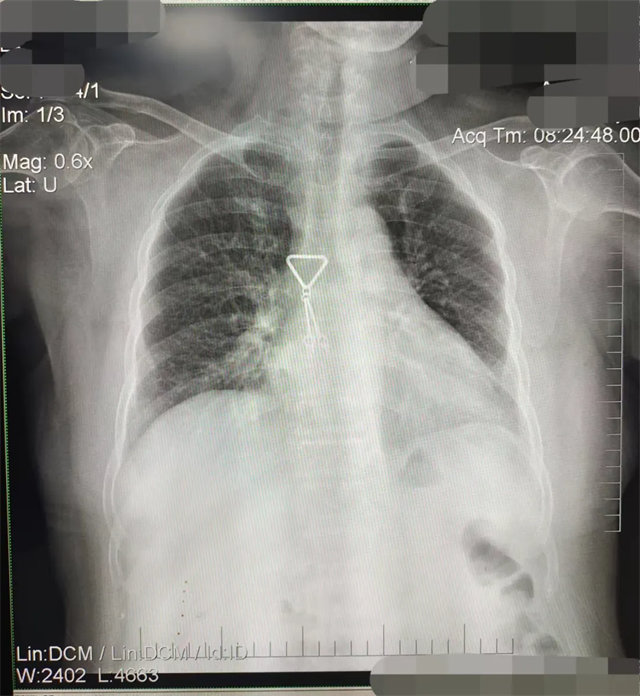

缺陷:雙側(cè)胸鎖關(guān)節(jié)不對(duì)稱,且有手機(jī)顯影。

解決:去除手機(jī)后,使患者左側(cè)緊貼成像件曝光。